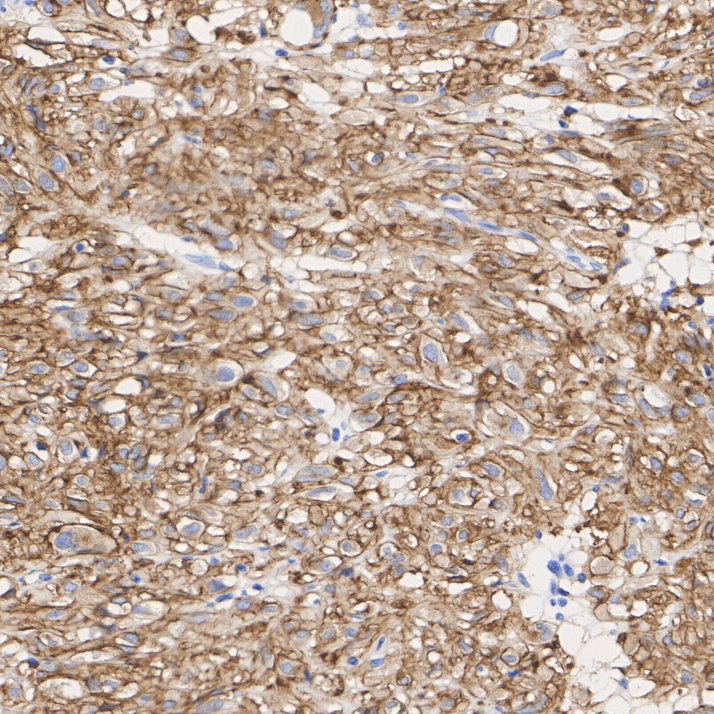

Immunohistochemical analysis of paraffin-embedded human gastrointestinal stromal tumor tissue with Rabbit anti-TMEM16A antibody (HA722719) at 1/2,000 dilution.

The section was pre-treated using heat mediated antigen retrieval with Tris-EDTA buffer (pH 9.0) for 20 minutes. The tissues were blocked in 1% BSA for 20 minutes at room temperature, washed with ddH2O and PBS, and then probed with the primary antibody (HA722719) at 1/2,000 dilution for 1 hour at room temperature. The detection was performed using an HRP conjugated compact polymer system. DAB was used as the chromogen. Tissues were counterstained with hematoxylin and mounted with DPX.